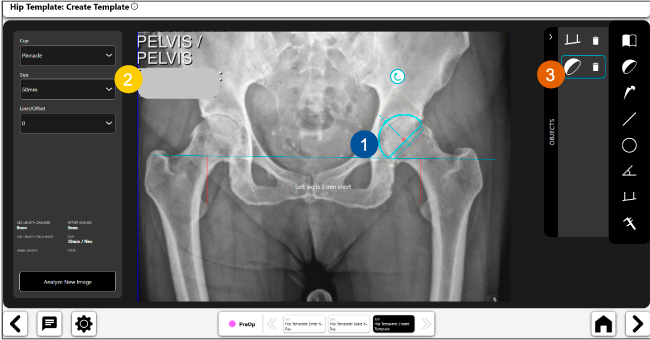

Nuestro navegador de cadera VELYS HIP NAVIGATION ™ es una solución digital que te acompañará a mejorar cada paso de las fases operatorias.

El sistema de navegación digital VELYS HIP NAVIGATION ™ para cirugía de cadera, es una tecnología innovadora y no invasiva diseñada para potencializar la toma de decisiones en tiempo real y basada en datos; aumentando la precisión y mejorando los resultados a corto, mediano y largo plazo para los pacientes.

Planeación preoperatoria mediante la creación de plantillas digitales para reemplazo de cadera y análisis intraoperatorio

Beneficios de la planeación preoperatoria con Velys Hip Navigation ™

• Disponibilidad de plantillas digitales de cadera.

• Expediente histórico y personalizado, optimiza la planeación con el calendario de casos realizados en Velys TM y utiliza los íconos interactivos para una rápida revisión.

• Espacio colaborativo: puede compartir los casos entre cirujanos y sus equipos mediante la funcionalidad de intercambio de información.